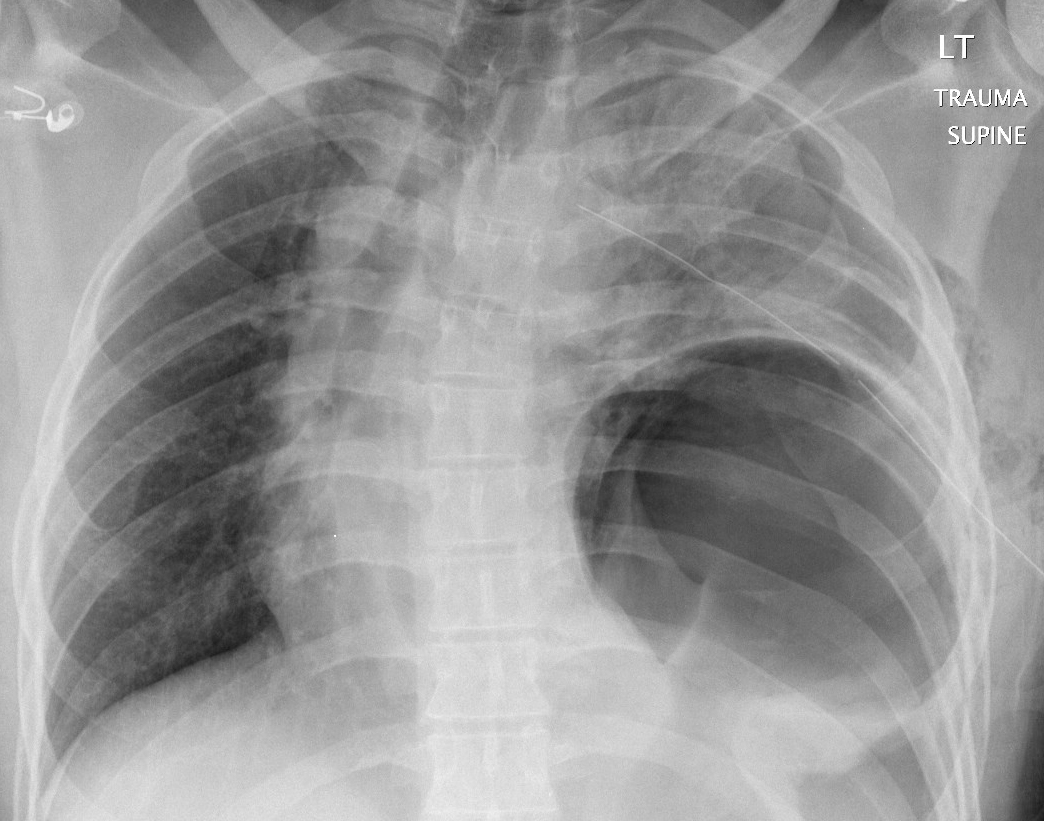

Gallery Blunt Chest Trauma Rupt HD Case 6a

Case 6a